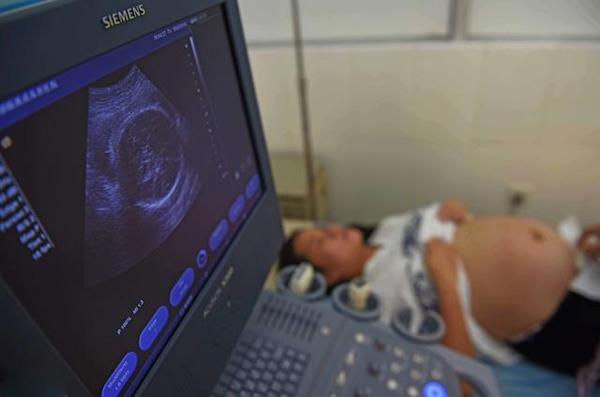

Sau khi khám và siêu âm, bác sĩ đã vô cùng hốt hoảng khi không thể tìm thấy nhịp tim của em bé.

Sau khi khám và siêu âm, bác sĩ đã vô cùng hốt hoảng khi không thể tìm thấy nhịp tim của em bé. Bác sĩ cho biết có thể thai nhi đã chết lưu trong bụng mẹ.